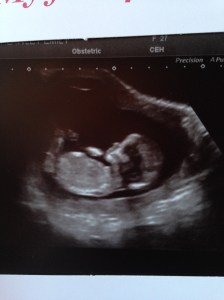

At Hull hospital you’re only allowed one person in with you at a time so Sam and I went in first. Stupidly, I thought they would be searching around for ages trying to find the teeny baby in my womb but practically two seconds after she put the probe on my tummy up popped a tiny baby on the screen! We were both so taken aback (I don’t know what we expected to see but it certainly wasn’t such a brilliantly clear image) and then, obviously, got a little teary-eyed at the first sight of our baby. It was amazing to finally have proof that there was definitely something in there and know everything was OK so far.

I thought I was 13 weeks +1 but by their measurements I was 13+3 meaning I went forward a week every Tuesday not Thursday…a very important point for my phone calendar where I am tracking my pregnancy’s progress, of course(!).